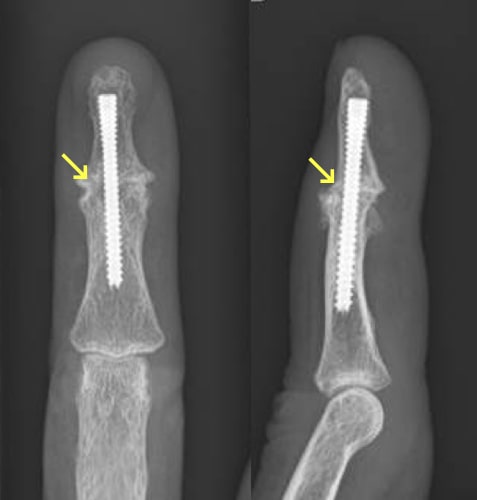

へバーデン結節

へバーデン結節写真

へバーデン結節術後写真

関節固定術後

原因

手指の第1関節(DIP関節)の変形性関節症であり、主に加齢性の変化と考えられます。

症状

DIP関節の痛みや腫れ、変形が進行します。特に水ぶくれのような腫瘤が生じることがあります(粘液嚢腫)。経過とともに、痛みは緩和することが多いですが、関節が動かしにくくなります。

治療方針

まずは、外用薬、テーピングなどの処方で様子をみます。痛みが強い場合には関節内注射をすることもあります。痛みが引かない場合や変形が目立って使い勝手が悪くなった場合は手術をします。手術は関節固定を行うことが多いです。